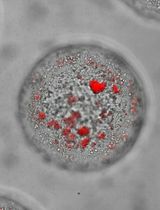

Stain the slides in TRAP Staining Solution for 30-45 min in an oven at 37°C. Monitor the color change every 15 min until the TRAP-positive area turns red.

Analyze osteoclast differentiation in TRAP stained slides

Scan whole TRAP stained tissue slides with an Olympus Hamamatsu NanoZoomer whole slide scanner at 40× magnification.

Use the Freehand Line tool in the NDP.view2 software to calculate the length of the interface between tumor and bone in tibial tumor samples. If multiple interfaces exist in the samples, calculate the sum of lengths.

Count the occurrence of TRAP positive cells at the tumor and bone interface.

Calculate the average occurrence of TRAP positive cells at the tumor and bone interface.

Show representative images with higher resolution as desired (Figure 3).

Figure 3. TRAP staining in 5-week tibial tumors. Shown are representative images of 2.5× (A, B), 10× (C), and 40× (D) magnifications of a PC-3 tibial tumor sample. Scale bars in A-B: 500 µm. Scale bar in C: 100 µm. Scale bar in D: 50 µm. T, tumor tissue. B, bone tissue. BM, bone marrow. M, muscle tissue. The lengths of tumor and bone interface were calculated in B using NDP.view2.